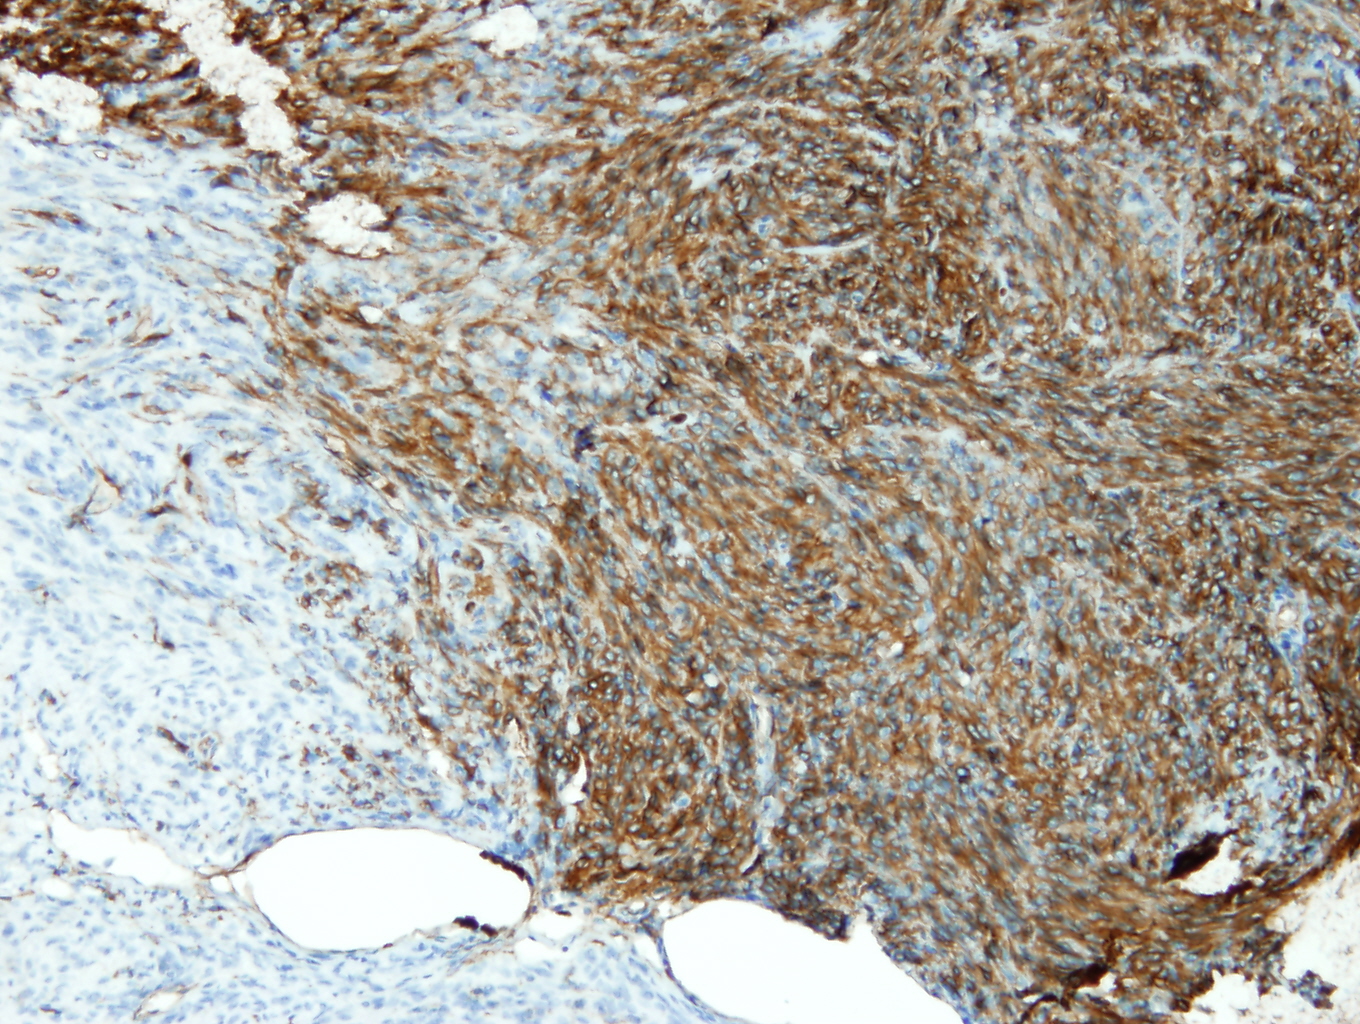

Anti-CD34

Králičia klonálna protilátka

Kód produktu:DB 151 Kategória:IHC-P

Aplikácia

IHC-P, riedenie 1:100

Galéria

db151a db151b